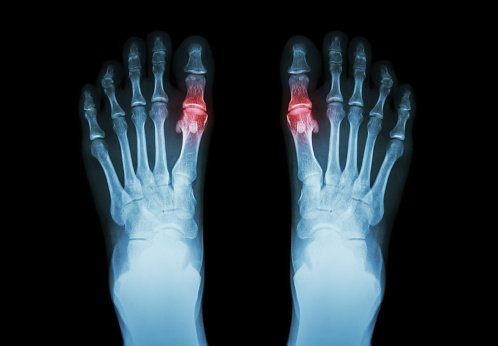

Hiperuricemia y tratamiento farmacológico de la gota

Butlletí d’informació terapèutica BIT. Vol. 30, núm. 2, 2019CatSalut, 10 de mayo de 2019Este Boletín revisa los tratamientos farmacológicos de los ataques agudos de gota y de la hiperuricemia haciendo un posicionamiento de los fármacos disponibles. Finalmente, se abordan diferentes controversias relacionadas con el tratamiento como el manejo de la hiperuricemia asintomática o la retirada del alopurinol.